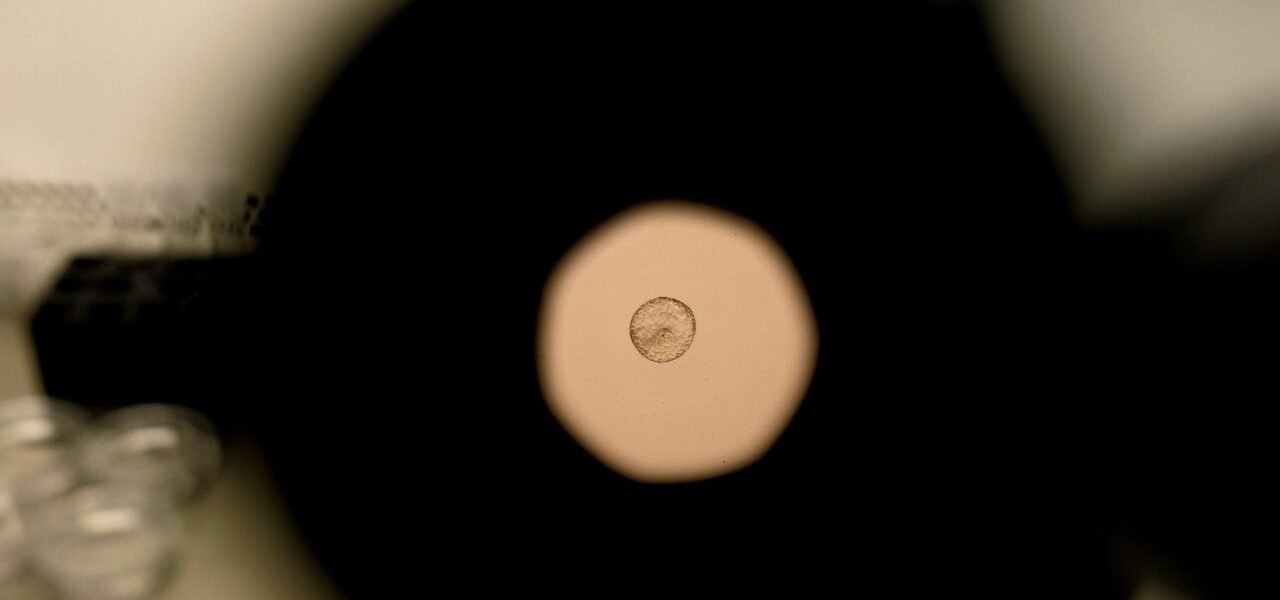

Por primera vez captan en video el momento exacto de la implantación de un embrión humano

Las observaciones permitieron apreciar cómo el embrión humano no se limita a adherirse, sino que se introduce activamente en la matriz extracelular, generando múltiples focos de tensión. “Observamos que el embrión tira de la matriz uterina, moviéndola y reorganizándola. También reacciona a señales de fuerza externas. Nuestra hipótesis es que las contracciones que ocurren in vivo podrían influir en la implantación del embrión”, explicó Amélie Godeau, coautora de la investigación publicada en Science Advances.